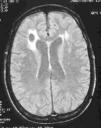

Síndrome de Diógenes: hallazgos neurorradiológicos en sustancia blanca. Base orgánica de las alteraciones del autocuidado en personas de edad avanzada

Diogenes syndrome: neuroradiology findings in white matter. Organic basis of self-care alterations in elderly people